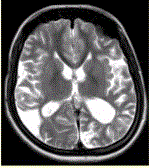

问题 女性,22岁。癫痫发作及智力异常。MRI显示见下图。 为进一步明确诊断,下一步的影像学检查首选

选项 A.MRI增强 B.FLAIR C.DWI D.MRA E.MRV F.DSA

答案 D

解析 D